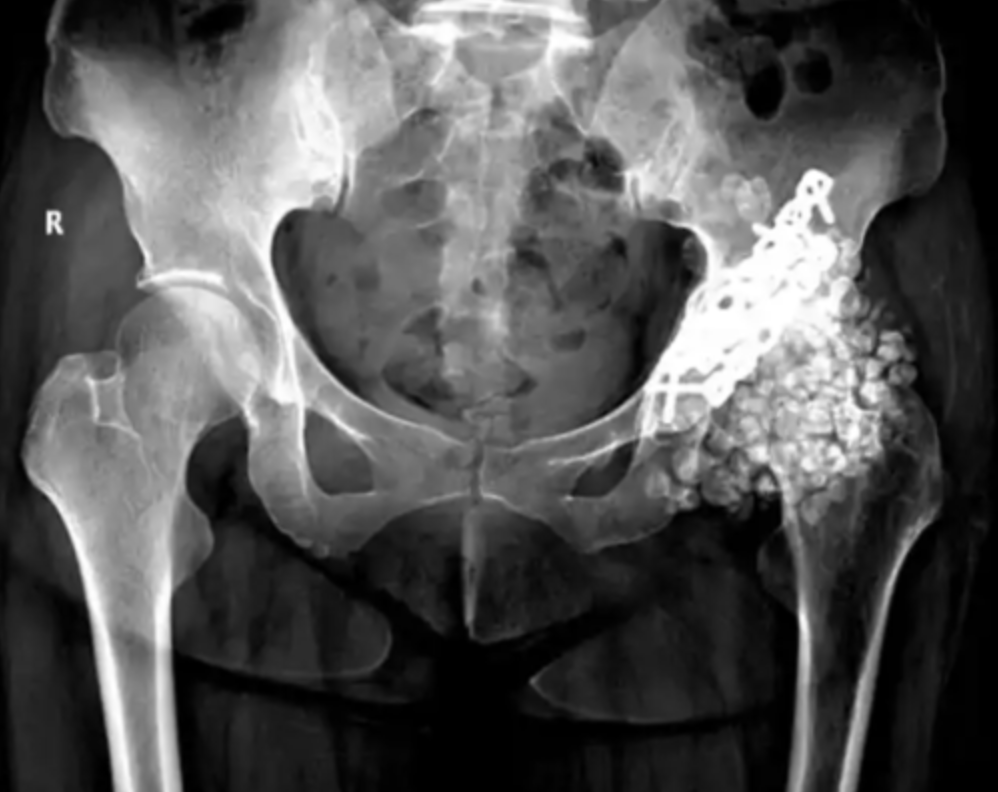

Kết quả chụp X-quang hông của người phụ nữ khiến các bác sĩ sốc nặng.

Bà Vương, một phụ nữ 40 tuổi đến từ Phúc Châu (Trung Quốc), gần đây bị đau hông dữ dội đến mức không thể đi lại được. Bà đến bệnh viện để kiểm tra và phát hiện mình có gần 300 khối u sụn ở khớp hông trái. Bác sĩ phẫu thuật vô cùng sửng sốt và cho biết tình trạng của bệnh nhân rất hiếm gặp, nhóm y tế đã nhanh chóng bắt đầu "cuộc chiến để lấy viên sỏi ra".

Theo truyền thông nước này, bà Vương đã gặp tai nạn xe hơi cách đây 10 năm, dẫn đến gãy xương hông trái nghiêm trọng. Mặc dù đã phẫu thuật để chữa trị, nhưng mô hoạt dịch ở khớp hông vẫn âm thầm "biến đổi" do ma sát trong nhiều năm. Cơn đau hông của bà gần đây ngày càng trầm trọng hơn và ảnh hưởng nghiêm trọng đến các hoạt động hàng ngày.

Bác sĩ cho biết kết quả chụp X-quang hông khiến các bác sĩ bị sốc. "Có gần 300 khối u sụn hoạt dịch với nhiều kích cỡ khác nhau trong khoang khớp háng của bà Vương, trong đó đường kính lớn nhất lên tới 2cm. Những 'sỏi khớp' này gây ra tình trạng viêm xương khớp nghiêm trọng, làm mòn đầu xương đùi và gần như không có khoảng trống giữa các khớp. Bà Vương được chẩn đoán mắc u sụn màng hoạt dịch khớp háng".

May mắn thay, bà Vương đã được cấp cứu kịp thời và ca phẫu thuật đã thành công tốt đẹp. Bác sĩ cho biết: "Để giải quyết vấn đề khớp hông, ngoài việc lấy sỏi ra, chúng ta còn cần phải tái tạo lại khớp ở phần tàn tích".

300 khối u sụn đã được nhóm y tế cắt bỏ